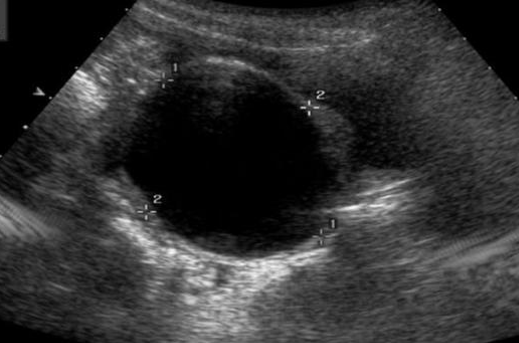

输卵管中的液性暗区

图片

图源:参考文献

输卵管积水:常由输卵管炎症引起,而输卵管炎性病变属于慢性盆腔炎的一部分。临床上多种因素均可导致盆腔炎而造成输卵管水肿、充血甚至管腔壁粘连,最终导致输卵管在不同的位置发生粘连闭锁。